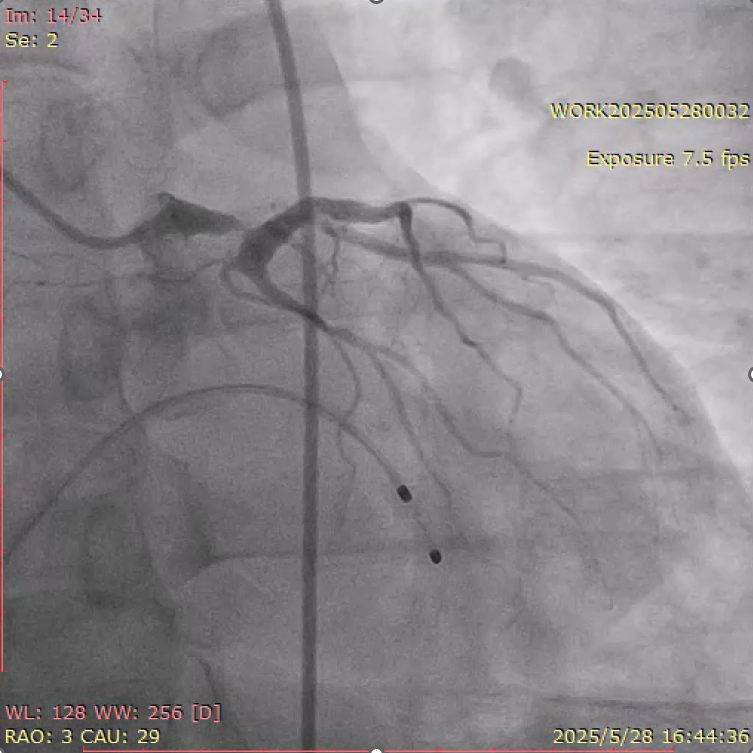

大会首日上午的“Best of Coronary Cases with the Masters”论坛中,首都医科大学附属北京朝阳医院心脏中心张智勇副主任医师作精彩病例分享,展示了一例左主干支架膨胀不全的高危复杂病变处理策略(图3)。

该病例由赵林教授团队主刀完成,团队在面对传统球囊扩张术难以奏效的复杂钙化背景下,创新性地联合应用冠脉旋磨术与震波球囊等多种手段,成功实现支架内足量扩张,保障了治疗安全性与有效性(图4-5)。

图4.术前左主干重度狭窄图

图5.PCI术后冠脉造影

张智勇副主任医师,在汇报中深入剖析了此类病变的高危复杂性与挑战性,并指出单一技术策略难以彻底解决此类复杂钙化病变所致的支架膨胀不全,系统阐述了旋磨、超高压球囊与IVL多技术协同的应用思路,展示了综合策略在优化左主干支架扩张及改善临床结局方面的独特价值。会议主席 Lombardi 教授高度评价了病例的复杂程度,对团队在重度钙化病变综合处理中的策略制定与精细操作给予充分肯定。病例展示引发现场强烈反响,国内外专家踊跃提问,会场座无虚席,充分体现了团队在复杂冠脉介入治疗领域的学术影响力与国际认可度。